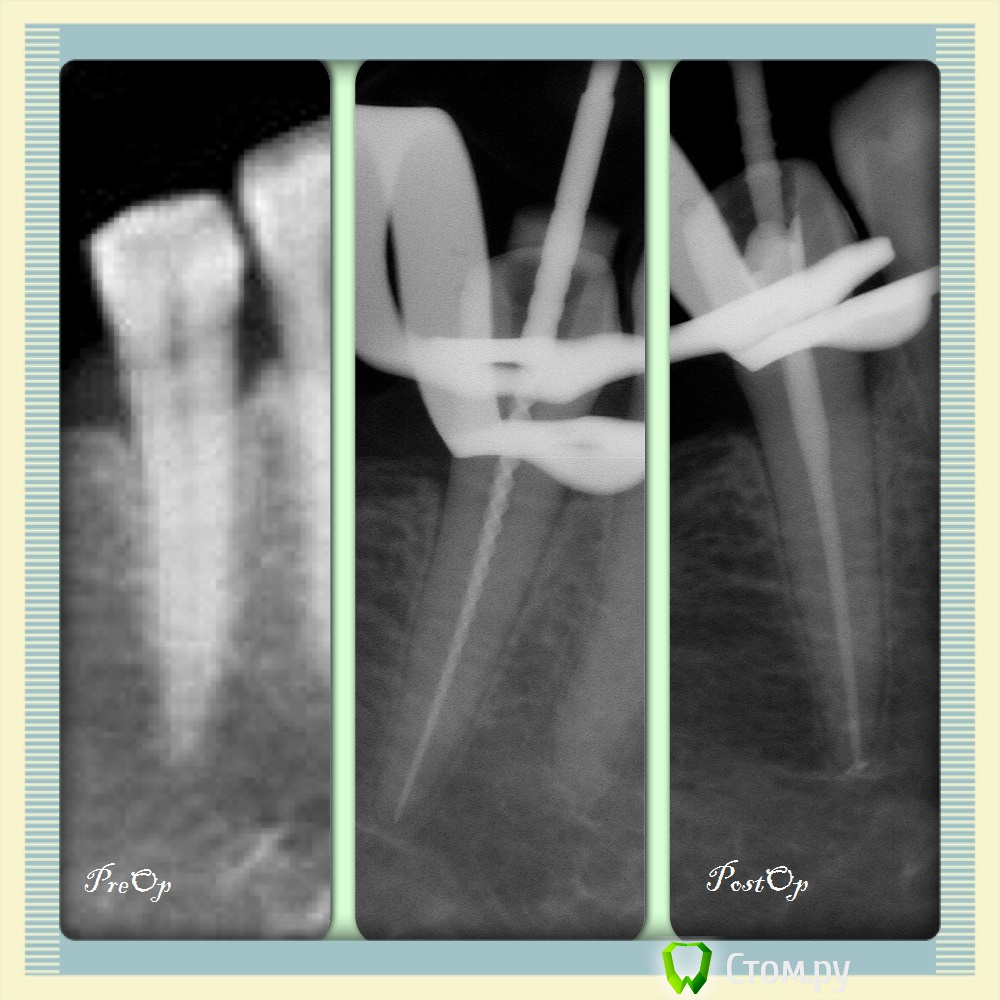

Ta.to4ka Опубликовано 18 февраля, 2014 Автор Поделиться Опубликовано 18 февраля, 2014 О!!! Получилось :-) Из последних 4.6, необратимый пульпит, жалобы были на самопроизвольные периодически возникающие боли, боль от холодного. Обработка профайлы+ ГХН 3,25%+УЗ, комбинированный метод обтурации 2 Ссылка на комментарий